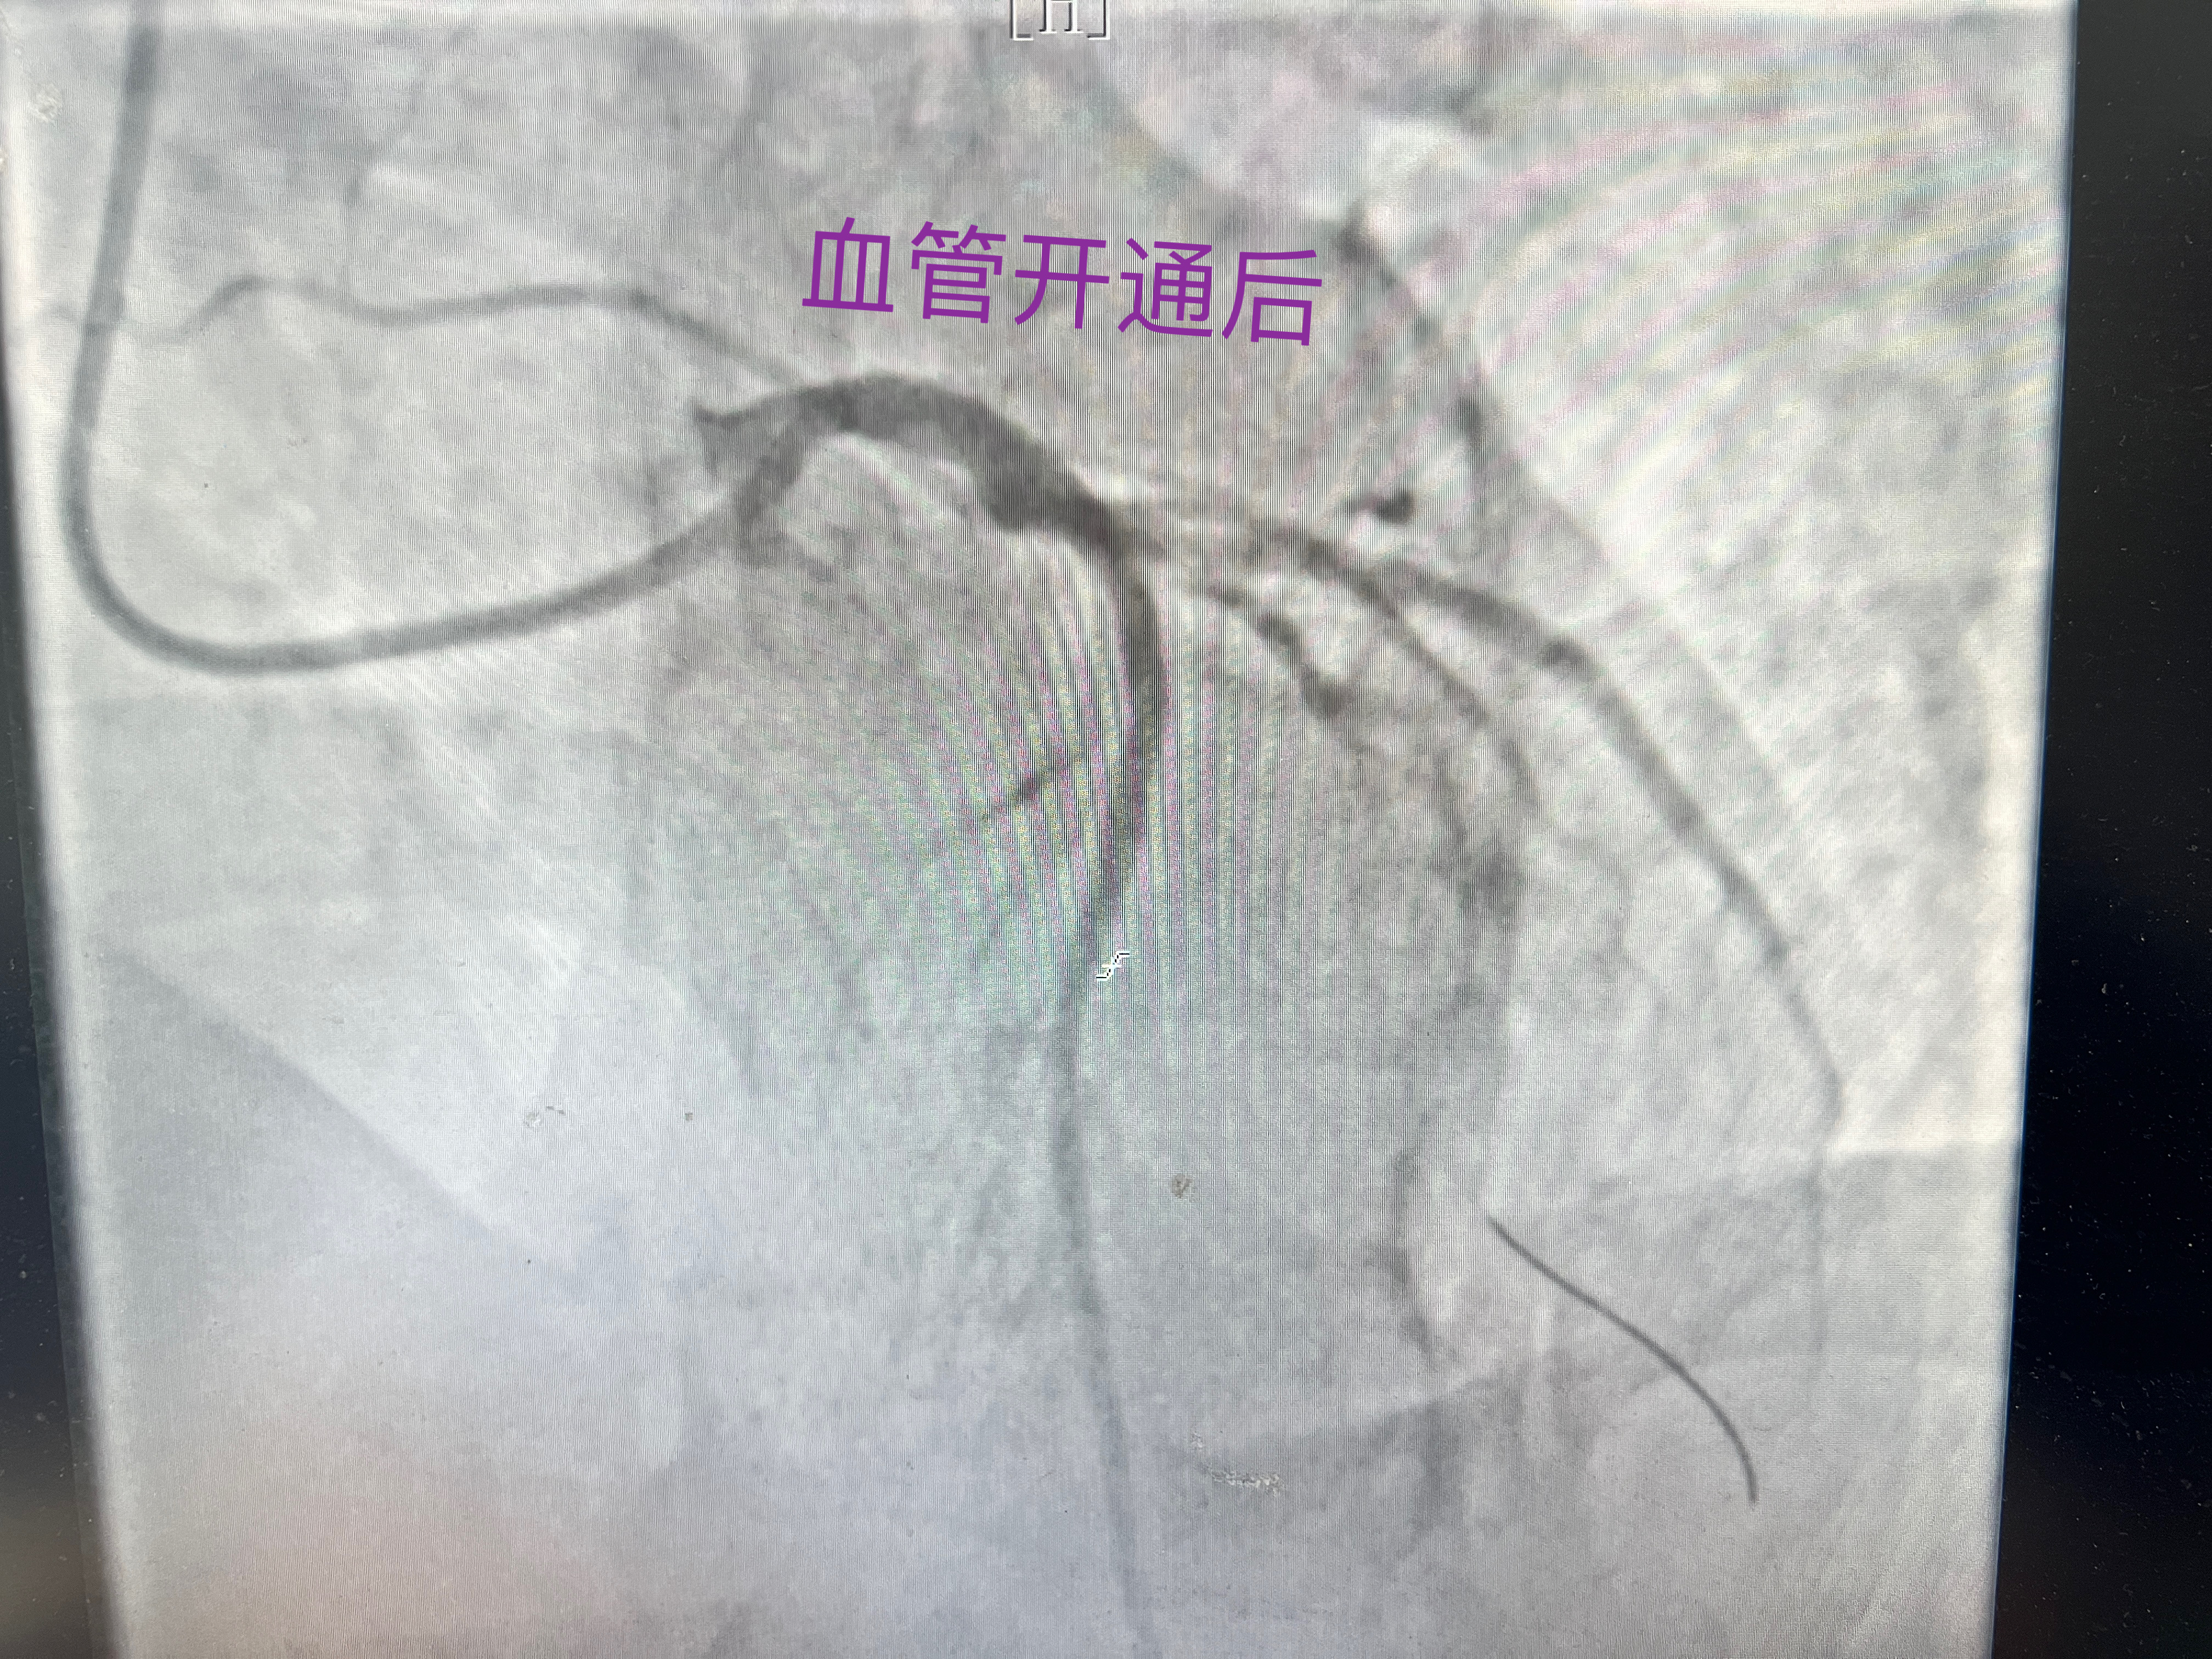

介入中心团队10分钟到达导管室开展紧急救治,经过了40分钟的精准手术,我院心血管内科介入团队开通了患者前降支近端狭窄95%的血管,顺利植入支架。术后,患者病情稳定,转入病房继续密切观察。